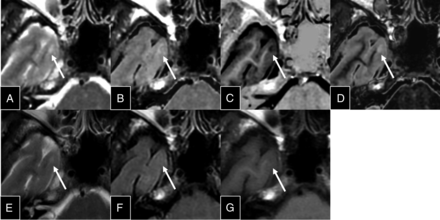

An experienced neuroradiologist (K.K.), blinded to the clinical information, individually counted the number of lesions in the synthetic and conventional image sets, which were shown in random order in 1 session. One synthetic image set included T2-weighted, FLAIR, DIR, and PSIR images for each patient (Fig 2). One conventional image set included T2-weighted, FLAIR, and T1IR images. Lesions at least 3 mm in diameter were counted. To confirm the accuracy of lesion counts, an experienced neuroradiologist (M.S.) also independently conducted MR imaging evaluations of the same imaging datasets. Conventional 3D DIR images and all other images were used as criterion standards by an experienced neuroradiologist (A.H.) to determine whether a counted lesion was a true- or false-positive and to classify the lesion according to its location as an infratentorial, deep GM, periventricular WM, deep WM, juxtacortical WM, or mixed WM-GM lesion. If a lesion was detected only on the conventional image set or the synthetic image set but not on conventional 3D DIR images, we defined it as a false-positive.

Representative sections of synthetic T2-weighted (A), FLAIR (B), PSIR (C), and DIR (D) images, along with conventional T2-weighted (E), FLAIR (F), and T1IR (G) images.

An MS plaque readily detected on PSIR and DIR images. This plaque (arrows) is difficult to identify on synthetic T2-weighted (A) and FLAIR (B) images and on conventional T2-weighted (E), FLAIR (F), and T1IR (G) images, but it is clearly delineated on synthetic PSIR (C) and DIR (D) images. The plaque was detected by a neuroradiologist (K.K.) on synthetic but not conventional MR images.

All the false-positives on synthetic images were located next to the CSF (Fig 5). In synthetic FLAIR and DIR images, the surface of the brain tends to become hyperintense, which is presumably caused by the partial volume effect. The surface of the brain is even brighter on synthetic DIR images than on synthetic FLAIR images (Fig 2). This feature may not be a problem if the existence of these artifacts is known in advance of reading synthetic MR images.